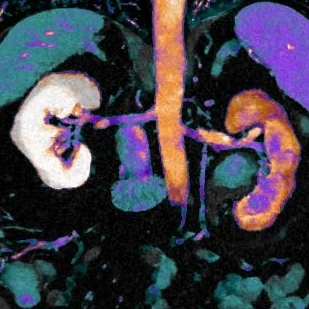

Conventioanl CT shows a filling defect in the left renal collecting system. Iodine uptake seen on the fusion image confirms vascular lesion. Note the delayed nephrogram on the left consistent with obstruction from the mass.

Iodine overlay with uptake confirms neoplasm